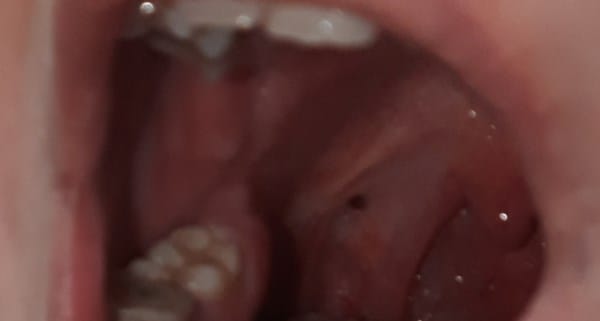

Hace algún tiempo me vi algo como una herida en el arco palatofaringeo, era roja y ahora es oscura, es pequeña y redonda, dudo de si en este momento esta más grande, me lo parece pero no puedo asegurarlo. A la vez tengo blanco en el arco palatofaringeo, en un lado más que otro, en el que más tengo me parece que se ha desplazado hacia atrás, ¿es eso posible? No lo sé. También tengo una herida en la parte de las encías que no se cura, es muy pequeña, me la vi como hace 3 semanas (No consigo que se vea bien en una fotografía para ponerla.) El síntoma que tengo relacionado con la boca/garganta es que me molesta al tragar, a veces me ha ocurrido y lo he relacionado con que había fumado de más, duraba un día o dos pero ahora se ha vuelto continuo. No tengo amígdalas así que no esta relacionado con algo de ellas. Soy fumadora de 2 paquetes diarios desde hace 10 años. ¿Todo esto estar relacionado simplemente con fumar o pueden ser síntomas de otra cosa? Empieza ha preocuparme.